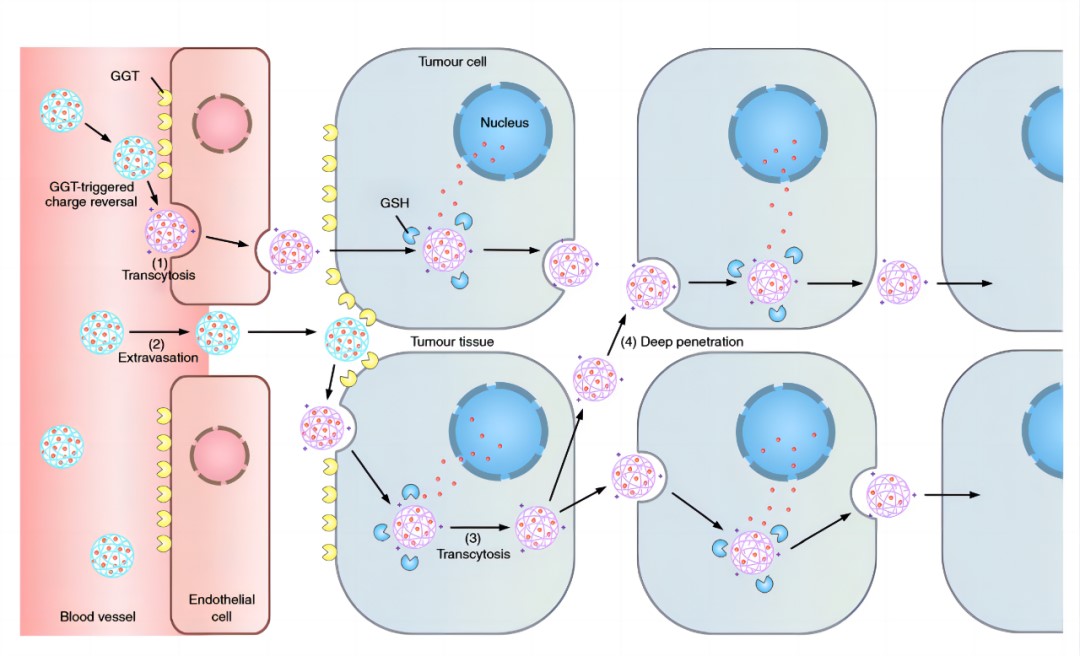

普利制药与浙江大学联合创制的胰腺癌纳米创新药PLAT001,首次构建了γ-谷氨酰转肽酶(GGT)介导的电荷反转聚合物,并将其应用于抗肿瘤药物的递送,突破纳米药物在实体瘤中的渗透性瓶颈。PLAT001目前已经获得中国和美国药物临床试验批件。